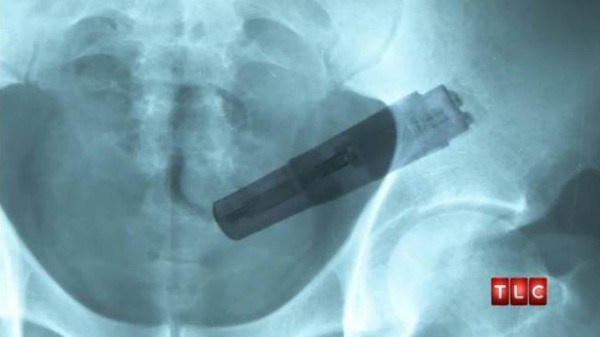

Mắc kẹt sextoy bên trong bộ phận sinh dục. "Tự sướng" bằng sex toy là kiểu tự sướng phổ biến nhất của cả phụ nữ và nam giới. Có thể nói, sex toy là thiết bị hỗ trợ hiệu quả cho những người muốn "đạt đỉnh". Tuy nhiên, nhiều người vì muốn tận hưởng cảm giác “sung sướng” cao độ nên đã lựa chọn mua những món đồ không phù hợp với mình. Không những thế trong quá trình "tự sướng" họ đã làm quá đà và mạnh tay khiến dụng cụ lọt thỏm bên trong. |